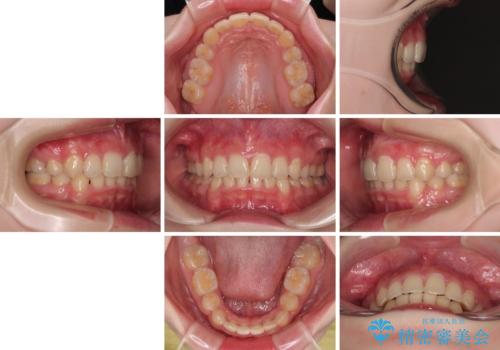

【モニター】デコボコと隠れてしまう前歯 ワイヤー装置による抜歯矯正で美しい口元に

- デコボコになっている前歯を気にして来院された患者様です。

口元の突出感は気になっていないものの、デコボコを解消すると口元が前方に突出する可能性があるため、上下左右の第一小臼歯4本を抜歯して、ワイヤー装置にて矯正治療を行うこととしました。

下の前歯が隠れてしまうほど深く咬みこんでいたため、上顎前歯が前方に突出しているような印象がありましたが、咬み合わせが改善され、整った口元に仕上げることができました。